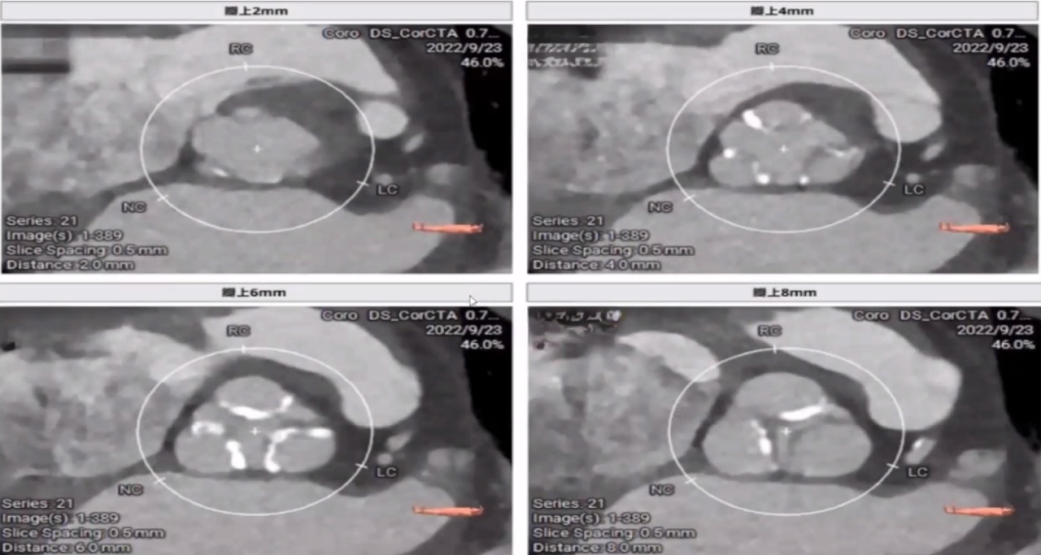

入院检查CT:冠脉CTA提示,左前降支近、中段管壁钙化及混合性斑块,管腔中度狭窄;左主干钙化性斑块,管腔轻微狭窄。左前降支中段心肌桥。主动脉硬化;主动脉瓣钙化灶。左心房、左心室增大。

患者术前冠脉CT评估收缩期:瓣环周长75.5mm,均径24.0mm(图左);左室流出道周长77.3mm,均径24.6mm(图右)。

舒张期:瓣环周长80.5mm,均径25mm(图左);左室流出道周长84.2mm,均径25.5mm(图右)。

该患者三叶瓣,钙化是以三个瓣叶为主的均匀钙化。

左冠高度16.4mm(图左),右冠高度16mm(图右)。冠脉风险评估较低。

左窦窦宽34mm,右窦窦宽30.7mm,无窦窦宽33.4mm(图左);窦管交界周长89.7mm,均径28.7mm(图右)。

升主动脉周长96.9mm,平均径30.6mm。

主动脉根部重建可见钙化集中在瓣叶的瓣缘上。

1.主动脉瓣狭窄主动脉根部评估如下:

瓣环周长75.5mm,平均径24mm;

流出道周长77.3mm,平均径24.6mm;

三叶瓣,重度狭窄,中度钙化,钙化主要分布于瓣叶,瓣叶纤维增厚;

左冠开口高度可,瓣叶长度可,窦宽相对瓣膜可;右冠开口高度可,瓣叶长度可,窦宽相对瓣膜可。冠脉风险低。